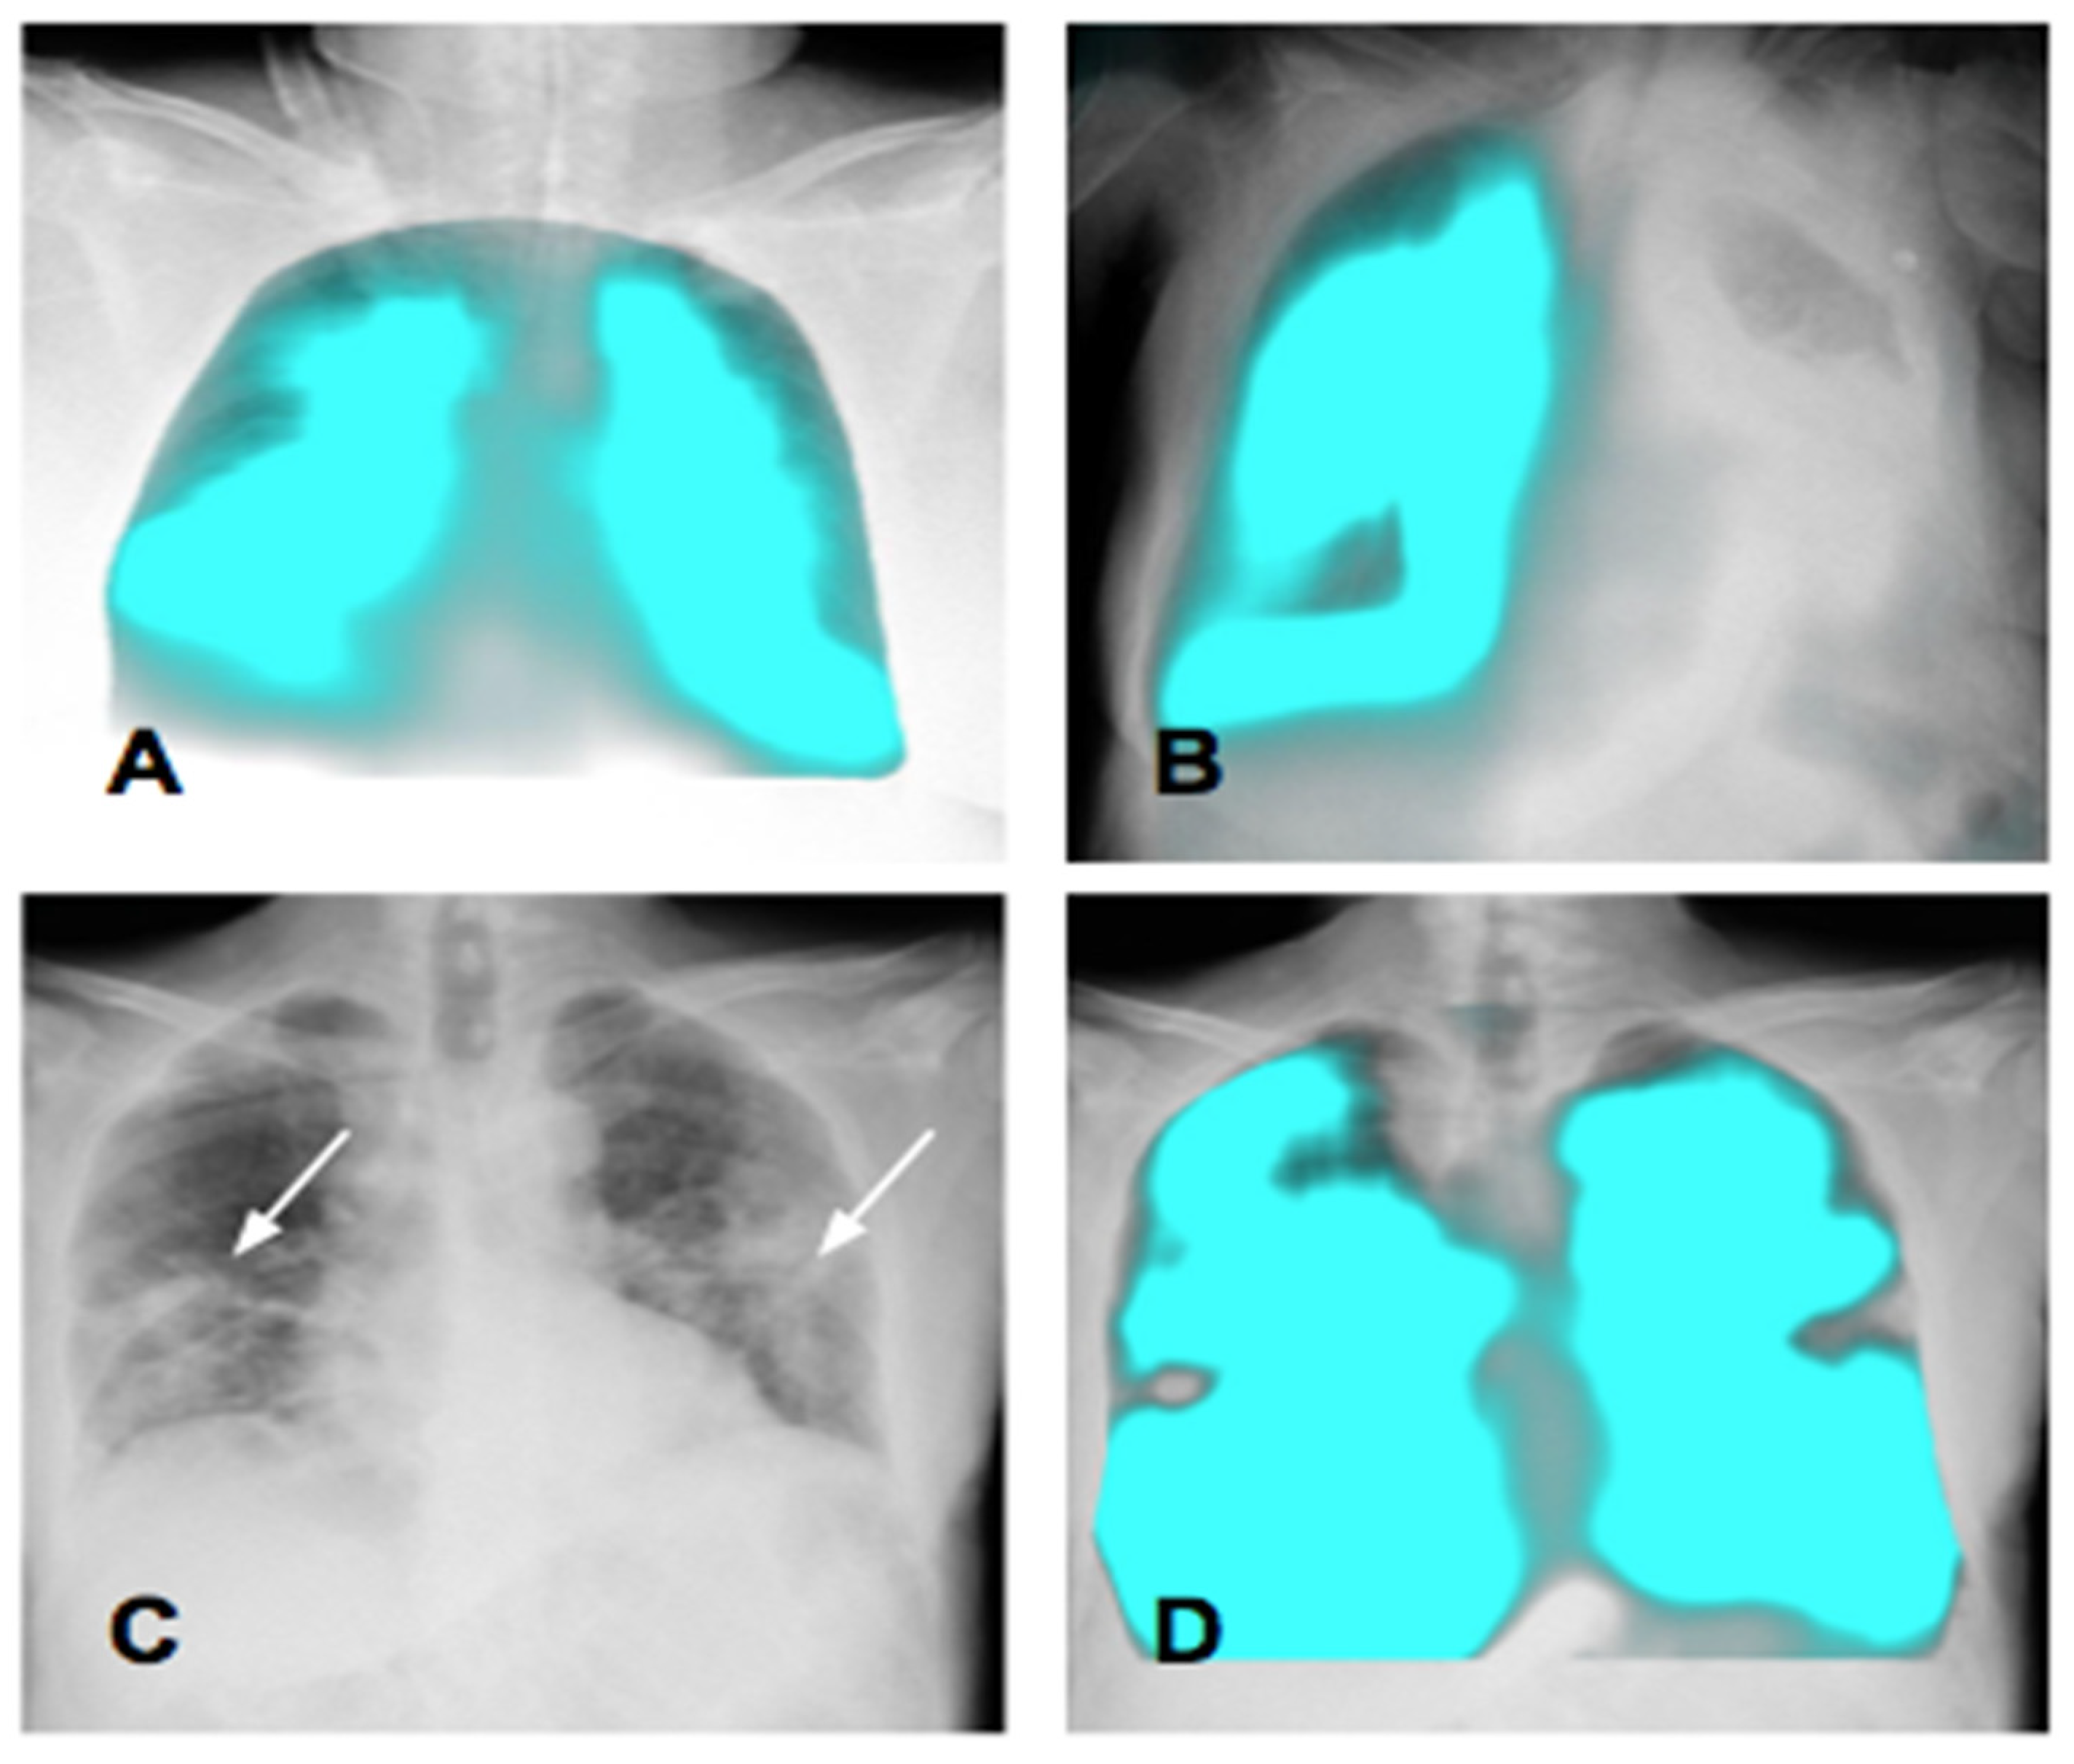

4. Calculation of the Lung Area

| DM-mode | Tracking diaphragm motion. Automatic calculation of the lung area and the relative changing rate (%). | Tracking of diaphragmatic domes represented in a motion–time graph. Area detection through an edge detection method in the post processing phase. | Diagnosis of diaphragm motion impairment and palsy. Automatic calculation of the respiratory rate. Analysis of lung dynamics in patients with restrictive/obstructive diseases. Follow-up of patients in pulmonary rehabilitation. |

| PL-mode | Color-coded map of the lung ventilation in different areas. | Analysis of the pixel values variations during the breath cycle. | Detection of regional differences in ventilation. Useful for the follow-up of therap, especially in Intensive Care Units. |